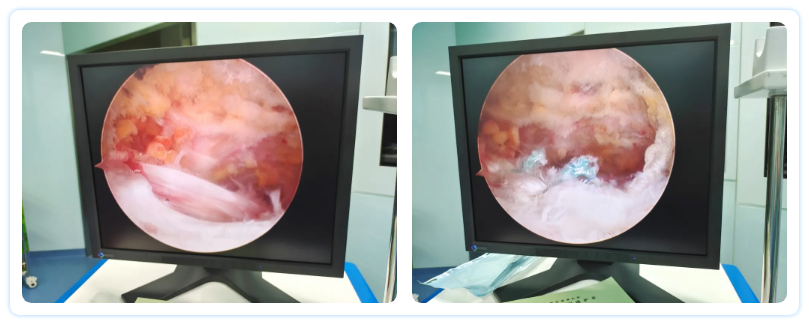

經(jīng)過完善的術(shù)前準(zhǔn)備,手術(shù)如期進(jìn)行。李樹鋒教授與方俊英主任帶領(lǐng)骨科手術(shù)團(tuán)隊開始了精細(xì)的手術(shù)操作,術(shù)中先行關(guān)節(jié)鏡下探查,確定了引起張奶奶右肩疼痛的主要原因:肩峰骨質(zhì)增生,長期磨損,導(dǎo)致肩關(guān)節(jié)大量炎性滑膜組織增生。專家們將異常增生的滑膜組織完整刨除后,進(jìn)一步探查肩袖,發(fā)現(xiàn)大約3厘米左右的“U”型裂口破損,專家們憑借豐富的手術(shù)經(jīng)驗和高超的操作技術(shù),將異常增生的肩峰磨平,用1枚帶線鉚釘為患者進(jìn)行縫合、修復(fù)撕裂的肩袖組織。整個手術(shù)過程醫(yī)護(hù)人員密切配合、精準(zhǔn)操作,僅用一個半小時便順利完成,體表僅有3個0.5厘米的切口,手術(shù)創(chuàng)傷微乎其微。術(shù)后張老太太恢復(fù)良好,僅僅住院3天,就康復(fù)出院了。